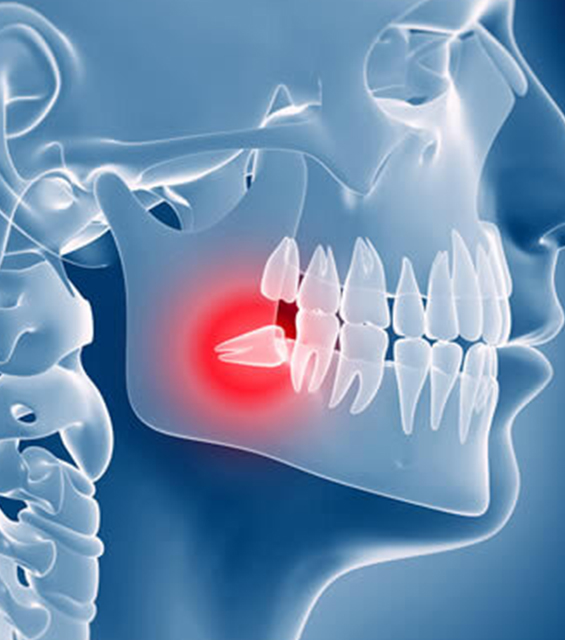

Removing eights

Eights are the teeth that give patients the most problems and inconvenience, especially when erupting in a position that prevents their complete eruption. Quite often, however, the problem is that they hardly fit in the mouth causing a lot of trouble. If the figure eight eruption has stopped and the tooth is invisible, its position is often incorrect, which can damage the roots of the remaining molars. Stopping may be painful and cause swelling. Additionally, eights are most prone to caries because access to them is difficult. This makes it much more difficult to clean them, and the food remaining in their vicinity causes the formation of bacteria.